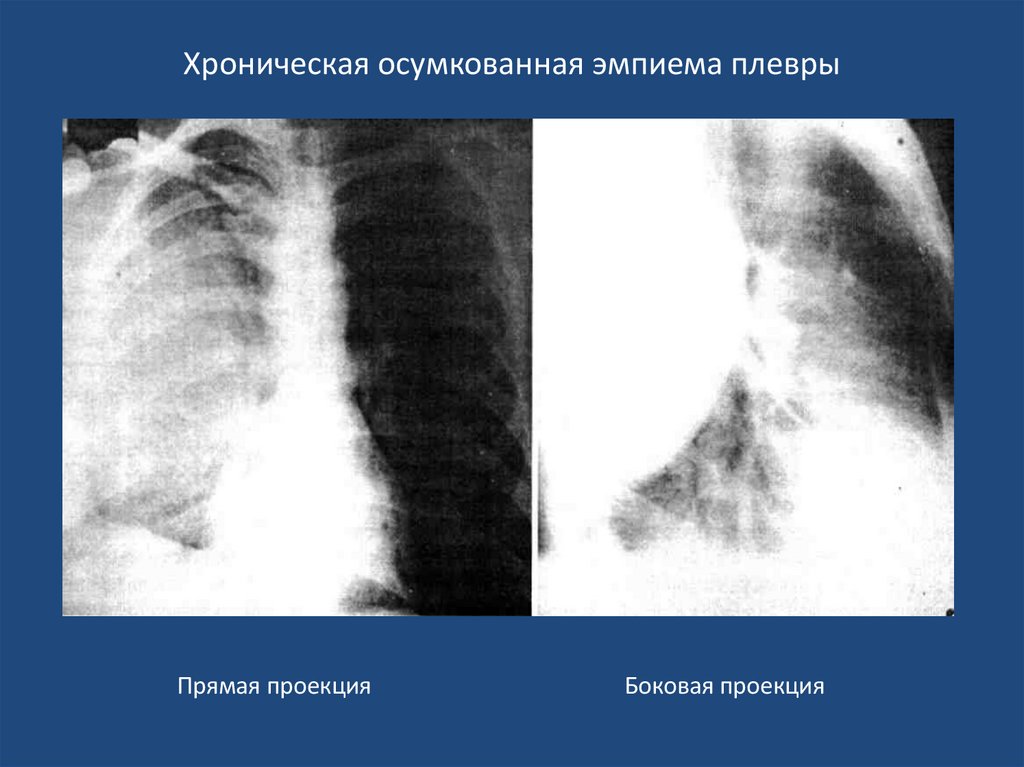

Хроническая осумкованная эмпиема плевры

Оперативное лечение при хронической эмпиеме плевры

38. Хроническая осумкованная эмпиема плевры

Прямая проекция

Боковая проекция